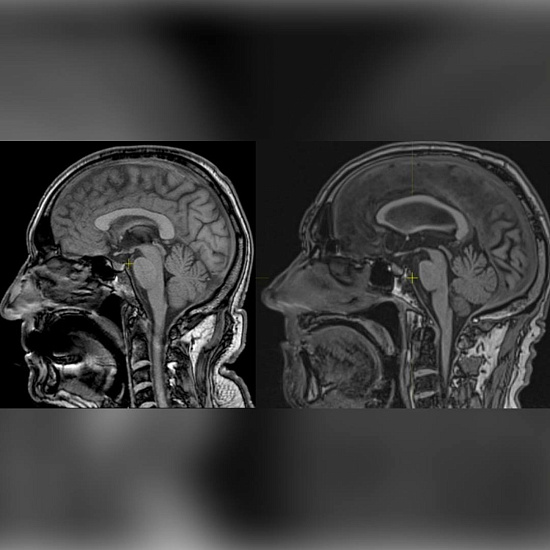

10 месяцев назад ему выполнили МРТ. Если сравнить получившийся снимок (картинка слева) со снимком другого 75-летнего пациента без аналогичных жалоб (картинка справа), можно рассмотреть атрофию языка. На осмотре наблюдается атрофия языка со множеством фасцикуляций (неконтролируемые кратковременные сокращения) не только в языке, но и в других мышцах тела.